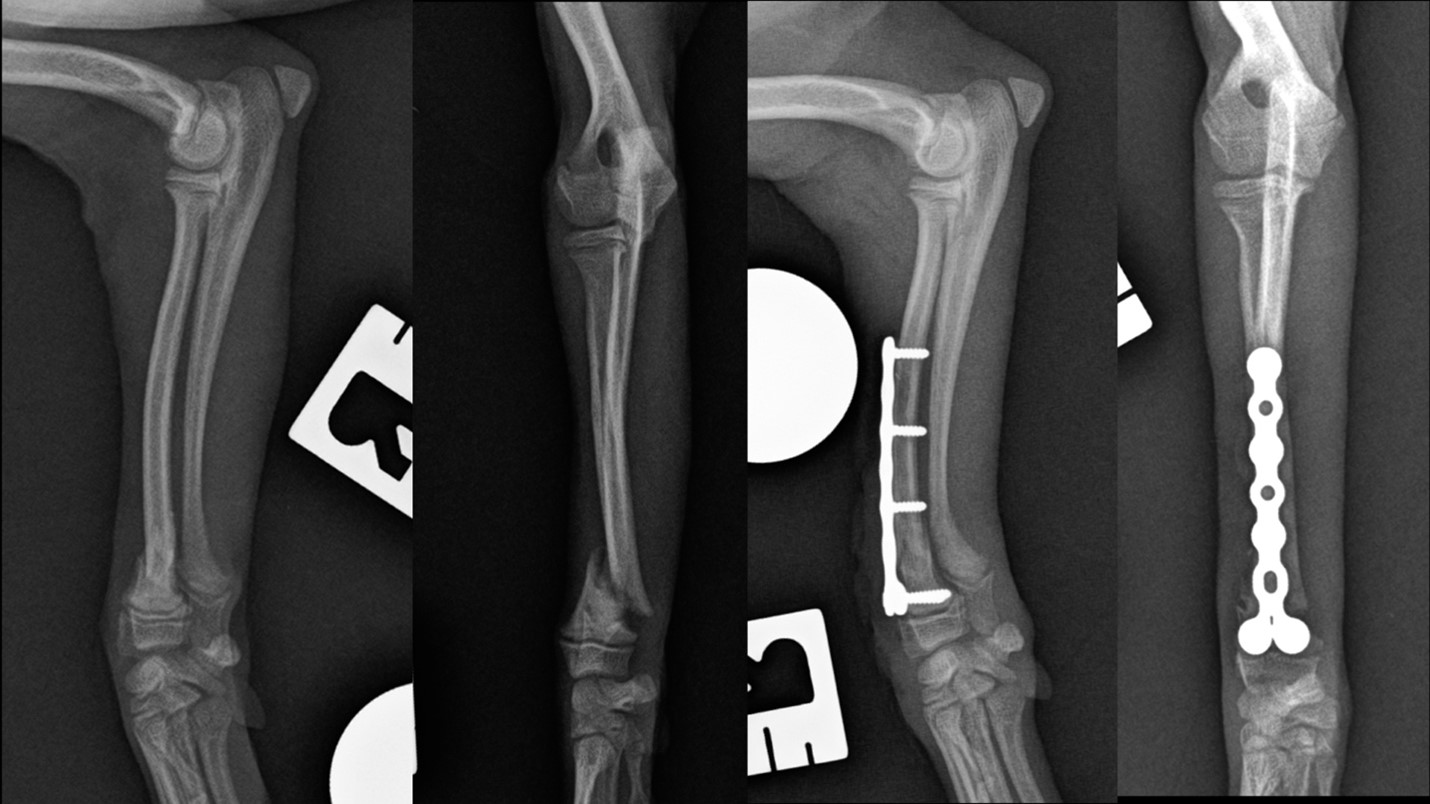

There are specific fracture configurations that seem to occur predominately in developing small breed dogs. An example of this are proximal tibial metaphyseal fractures (also called proximal metaphyseal curvilinear tibial fractures). They seem to occur predominately in immature small dogs. The reported outcomes and relatively high complication rates in recent publications have highlighted the challenges these fracture configurations represent and a need to better understand the pathobiology and ideal treatment recommendations. Descriptions of plating, pinning, external skeletal fixation and non surgical management have been described. Although most fractures will heal, mostly due to the juvenile biology (so called ‘healing machines’), limb function can be compromised if a tibial deformity occurs.

Any implant we may want to use must be correspondingly small. The implants that have traditionally been available have not always necessarily been compatible with the kind of bone size that is characteristic of toy breed dogs. There has been a relative explosion of smaller implants from a range of different veterinary implant manufactures from around the world in recent years.

For instance, in 2020, the AO Technical Commission, gained approval for the Synthes mini fragment plates. These plates are smaller than traditional ones and the tolerances and precision required for successful application exist on a very narrow spectrum. And it is of course equally important for colleagues to understand that these new implants exist and under which circumstances they should select a certain size implant over another. Locking and non locking internal fixation systems are now accessible from as small as 1.0mm.